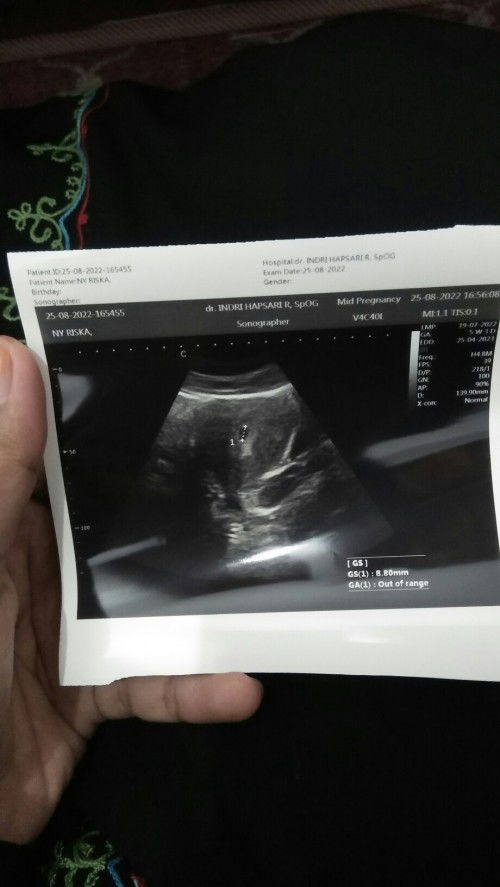

Hamil 5w6d pernah sekali keluar lendir pink